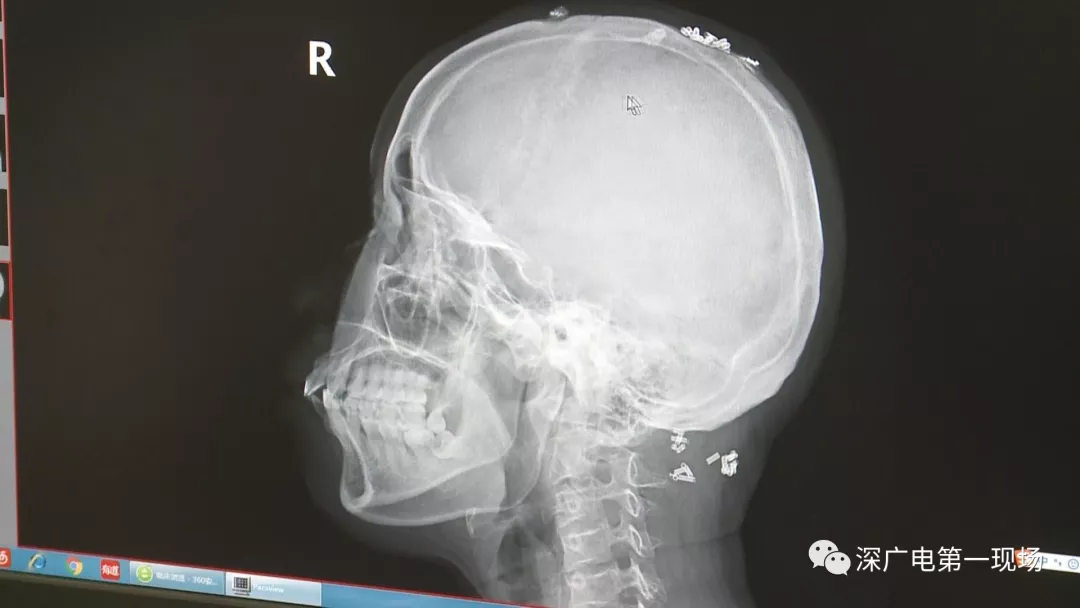

從X光影像圖片中可以看到

患者周身布滿了彈簧圈

深圳大學(xué)總醫(yī)院神經(jīng)外科副主任醫(yī)師陳富勇介紹,當(dāng)時(shí)檢查的時(shí)候發(fā)現(xiàn),該患者從頭部到腿部,基本上每個(gè)地方都有彈簧,很難數(shù)清具體數(shù)目。